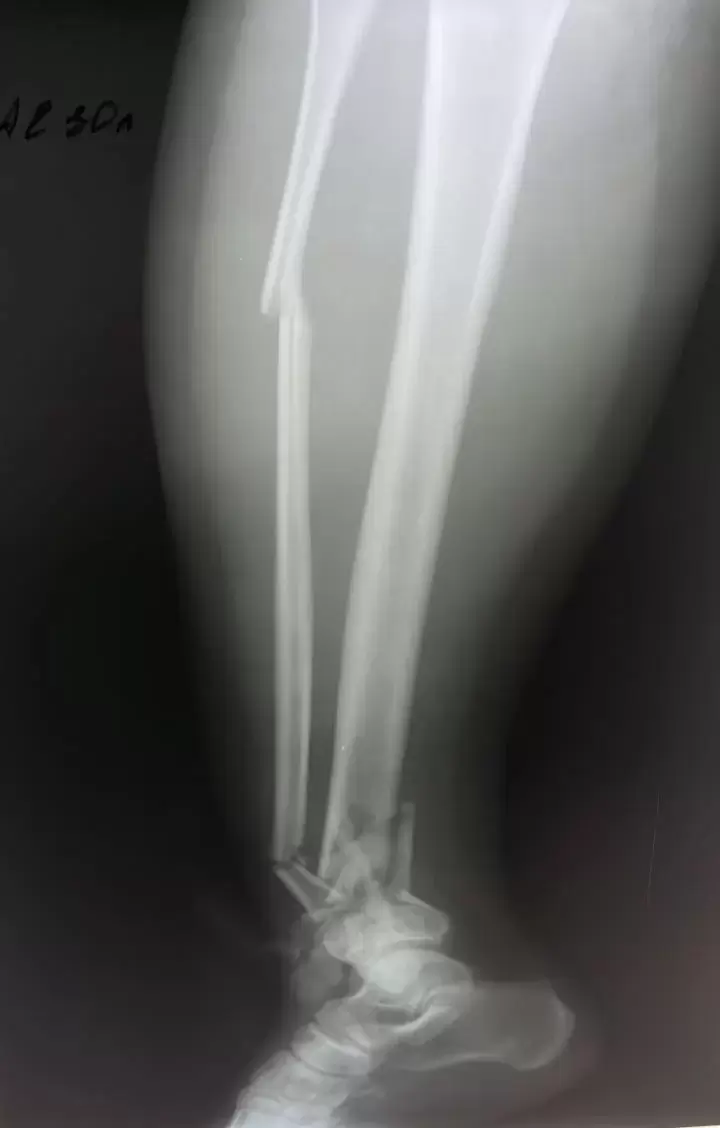

Как сообщает "Вести: Приморье" со ссылкой на Минздрав Приморья, благодаря оперативной и слаженной работе бригады скорой медицинской помощи удалось спасти молодую девушку с крайне тяжёлыми травмами. Пострадавшую экстренно доставили в Спасскую городскую больницу, в травматологическое отделение. Состояние пациентки оценивалось как крайне тяжёлое: травматический шок, открытые переломы костей голени, множественные переломы таза, обширные рваные раны нижних конечностей.

После стабилизации состояния врачи провели сложнейшее оперативное вмешательство — выполнены наружная и внутренняя фиксация переломов таза и голени, лапароскопия для исключения повреждений внутренних органов, а также первичная хирургическая обработка ран. Операция прошла без осложнений», – рассказали специалисты больницы. После этапа реанимации, по согласованию с краевыми медицинскими учреждениями, пациентку перевели в Краевую клиническую больницу №2 для дальнейшей реабилитации.